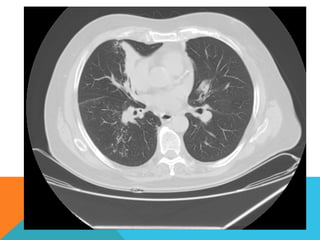

ABORDAJE TÉCNICO: Se realiza estudio con ventana mediastinal y de parénquima pulmonar con técnica de ALTA

RESOLUCION, en inspiración y espiración, mediante  cortes axiales, desde ápices hasta bases pulmonares, con las

siguientes observaciones

En las partes blandas y las estructuras óseas dentro de los límites de la normalidad. Las regiones axilares libres.

Ambos pulmones con neumatización conservada, con sobredistensión pulmonar, y áreas de atrapamiento aéreo,

bilateral con cambios fibrosos cicatriciales apicales derechos. Se demuestran áreas de condensación en topografía

predominantemente parenquimatosa pulmonar derecha, la mayor de ellas evidenciada hacia la base, acompañada

de broncograma aéreo, la medición máxima al corte axial de 6.1 por 2.2 cm, en topografía del segmento posterior

del lóbulo inferior, S10 así como también otra más se definen topografía de similares características en topografía

del segmento medial del lóbulo medio, S5. En topografía parenquimatosa pulmonar izquierda imagen de similares

características a las ya descritas en topografía del segmento lingular inferior, S4.

No hay derrame ni áreas de engrosamiento pleurales.

El patrón vascular es de características normales donde no se delimitan imágenes de lesiones aneurismáticas

únicamente cambios por aortoesclerosis incipiente.

El corazón de dimensiones conservada, de contornos regulares, sin desplazamientos; en la región hiliar derecha se

define adenopatía de medición máxima corte axial de 1.6 por 1.4 cm.

ABORDAJE TÉCNICO: Serealiza estudio con ventana mediastinal y de parénquima pulmonar con técnica de ALTA RESOLUCION, en inspiración y espiración, mediante  cortes axiales, desde ápices hasta bases pulmonares, con las siguientes observaciones En las partes blandas y las estructuras óseas dentro de los límites de la normalidad. Las regiones axilares libres. Ambos pulmones con neumatización conservada, con sobredistensión pulmonar, y áreas de atrapamiento aéreo, bilateral con cambios fibrosos cicatriciales apicales derechos. Se demuestran áreas de condensación en topografía predominantemente parenquimatosa pulmonar derecha, la mayor de ellas evidenciada hacia la base, acompañada de broncograma aéreo, la medición máxima al corte axial de 6.1 por 2.2 cm, en topografía del segmento posterior del lóbulo inferior, S10 así como también otra más se definen topografía de similares características en topografía del segmento medial del lóbulo medio, S5. En topografía parenquimatosa pulmonar izquierda imagen de similares características a las ya descritas en topografía del segmento lingular inferior, S4. No hay derrame ni áreas de engrosamiento pleurales. El patrón vascular es de características normales donde no se delimitan imágenes de lesiones aneurismáticas únicamente cambios por aortoesclerosis incipiente. El corazón de dimensiones conservada, de contornos regulares, sin desplazamientos; en la región hiliar derecha se define adenopatía de medición máxima corte axial de 1.6 por 1.4 cm.